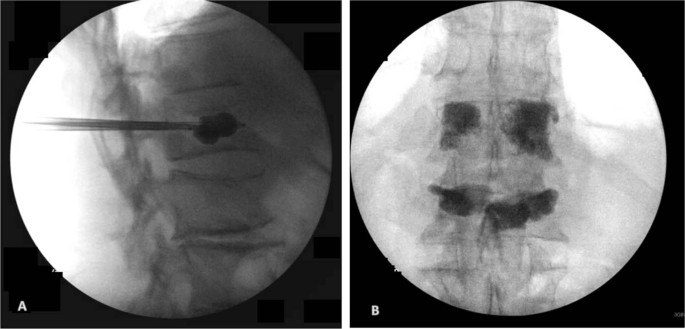

An 82-year-old male presented with a remote history of prior falls and a recent traumatic compression fracture of his L1 vertebral body. He reported no previous fractures, weight loss or antecedent pain. He was initially treated with a brace and underwent physical therapy. At follow-up, he had no neurological deficits but demonstrated severe recurrence of pain with progressive functional impairment refractory to conservative management. An MRI showed a worsening L1 vertebral body collapse, a T12 inferior endplate fracture, and a L2 superior endplate fracture (Fig. 1). The imaging was suspicious for a pathologic etiology. With his intractable pain and collapse at the thoracolumbar junction, we proceeded with a kyphoplasty of L1, vertebroplasty of T12, and obtained a bone biopsy for pathology and culture (Fig. 2). The initial smear testing for acid-fast bacilli (AFB) was negative with an interim negative report at 2 weeks, and final identification of M. abscessus at 6 weeks. The infectious disease (ID) service was consulted for further management. The smear was presumed to be a contaminant given his history and presentation.